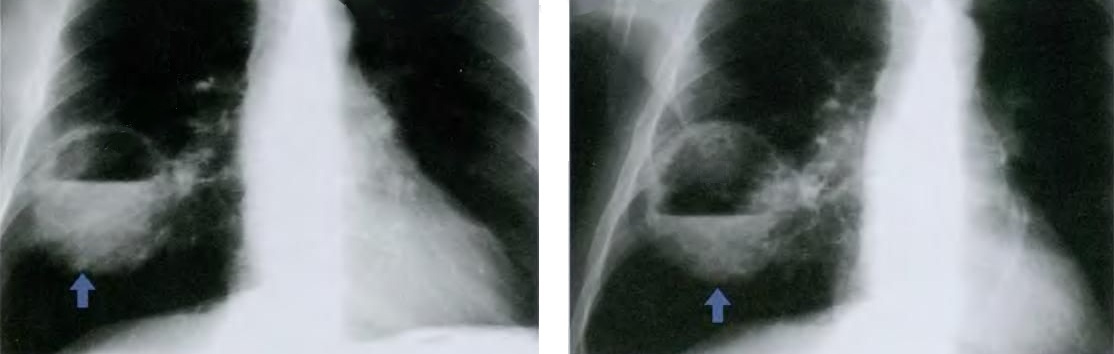

Из инструментальных методов диагностики может проводиться рентгенография органов грудной клетки, компьютерная томография и фибробронхоскопия.